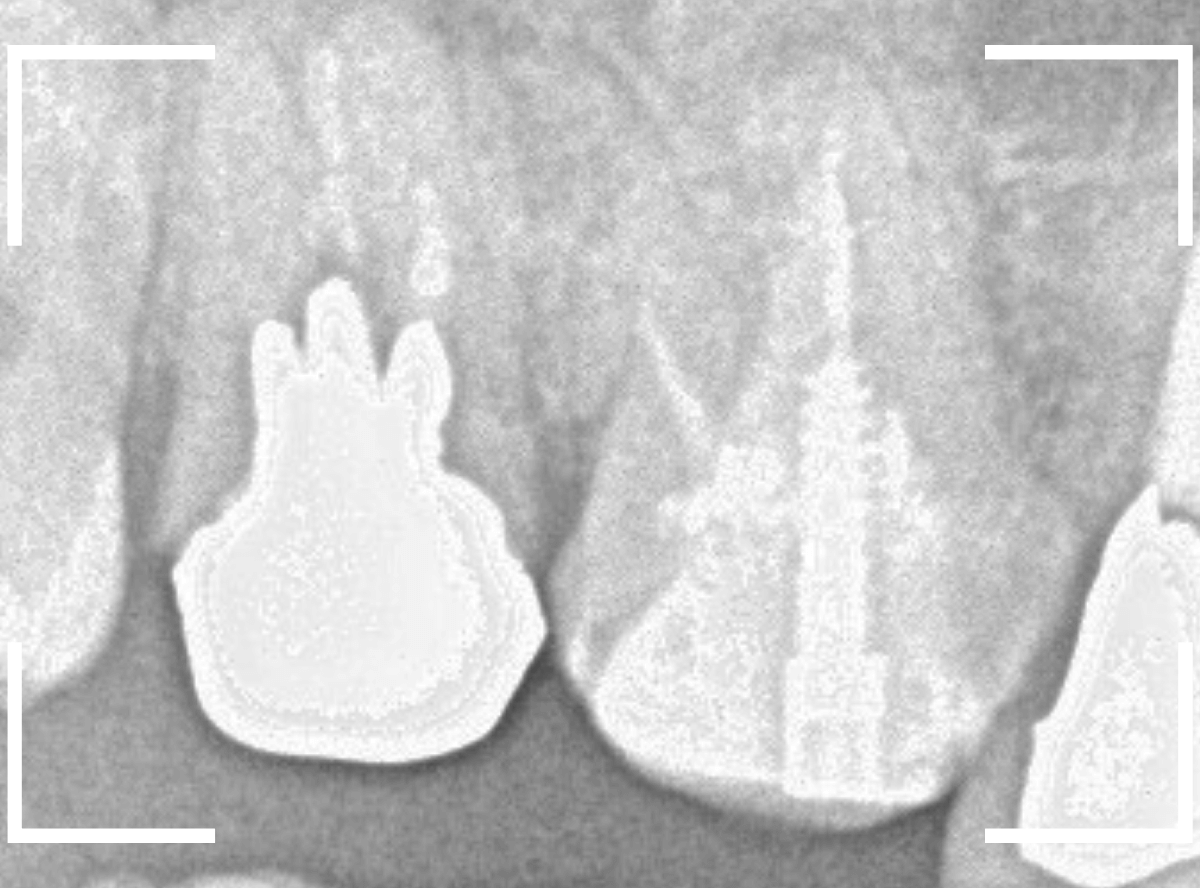

レントゲン写真で確認します。

左側のメタルコアの内側も少し虫歯がありそうな気がします。

できるだけ土台を外すリスクは避けたいのが本音ですが、治療から長期間経っていることもあり、両歯とも土台を外して再治療する事になりました。

レントゲン写真で確認すると、歯の奥側が虫歯になり始めています。